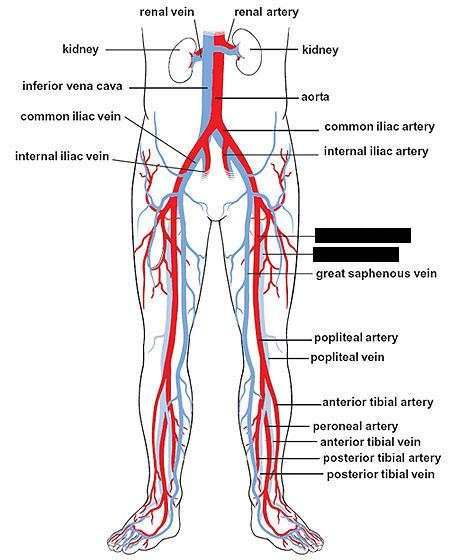

Anterior tibial artery/vein

Posterior tibial artery/vein

Common iliac artery/vein

Femoral artery/vein

Great saphenous vein

Internal/external iliac artery/vein

Popliteal artery/vein

Renal artery/vein